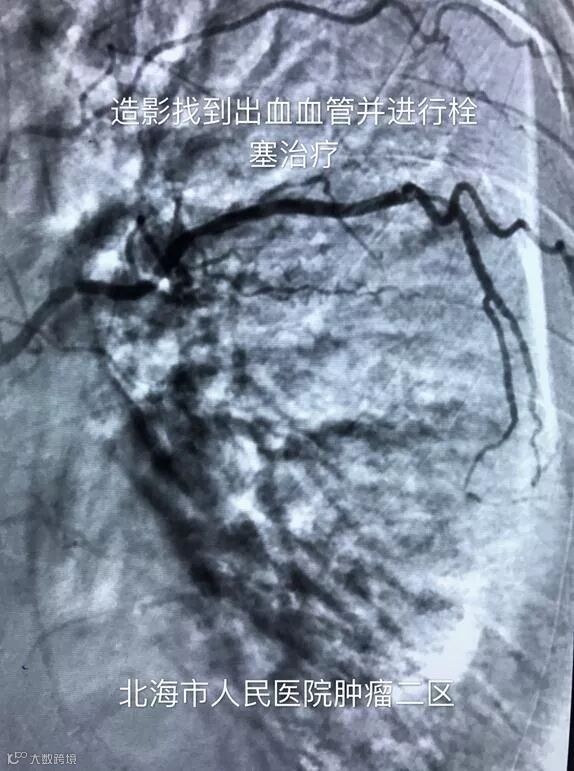

通过临床表现结合化验结果,张成文考虑这是合并化疗的四度骨髓抑制,凝血功能差,且咯血量大,保守估计已超过一千毫升,病情十分危重!这种情况试图通过药物止血几乎是不可能的,也无法做外科手术,唯一的救命办法就是通过急诊介入栓塞住出血的血管。

张成文说,在这种凝血功能差的情况下做介入手术风险是极大的,病人随时可能突然大咯血而窒息死亡,抢救生命刻不容缓。于是和病人家属沟通同意后马上送到介入室进行手术,医务人员在手术过程遇到了考验:股动脉起始段迂曲,导管推进困难;反复造影未发现支气管动脉发出;

患者在术中仍不断咯血等困难,但最终经过两个多小时的努力,张成文等人还是通过丰富的临床经验和精湛的技术找到出血的血管并成功栓塞,手术结束时患者咯血立即停止。